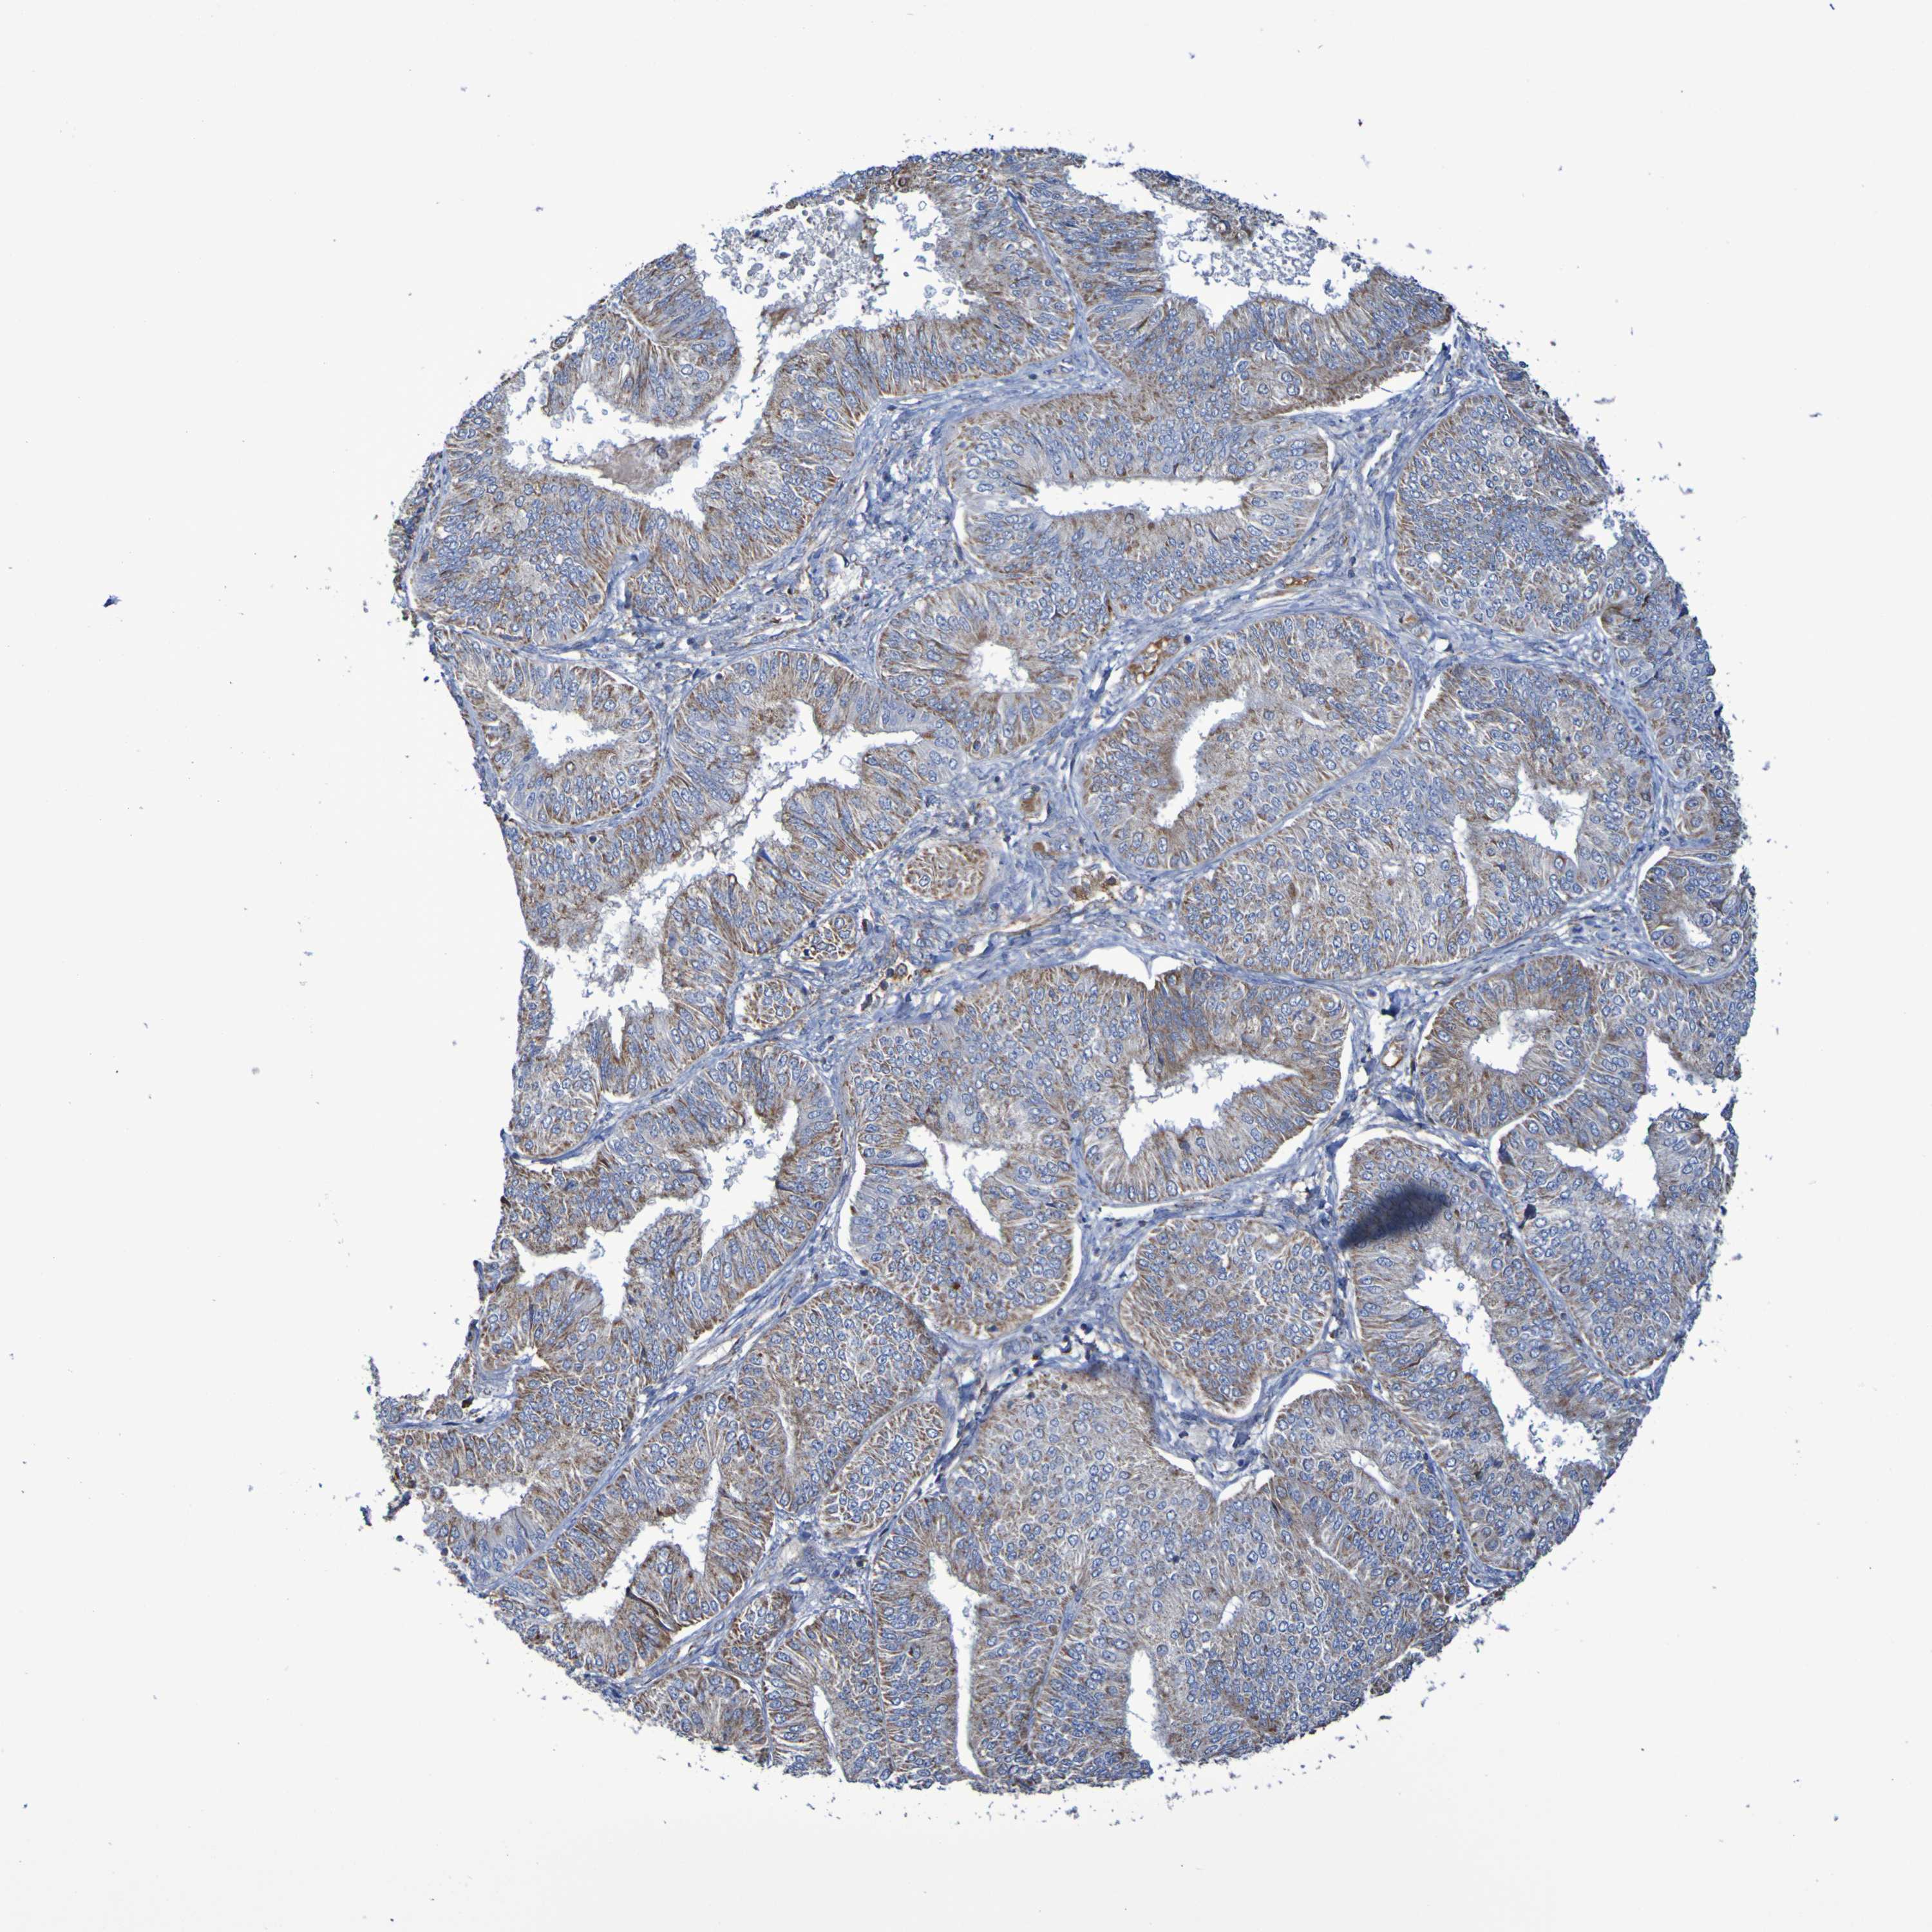

ENDOMETRIAL CANCER - Protein expressioni

A mouse-over function shows sample information and annotation data. Click on an image to view it in a full screen mode. Samples can be filtered based on level of antibody staining by selecting one or several of the following categories: high, medium, low and not detected. The assay and annotation is described here.

Note that samples used for immunohistochemistry by the Human Protein Atlas do not correspond to samples in the TCGA dataset.

Antibody stainingi

Antibody staining in the annotated cell types in the current human tissue is reported as not detected, low, medium, or high, based on conventional immunohistochemistry profiling in selected tissues. This score is based on the combination of the staining intensity and fraction of stained cells.

Each image is clickable and will lead to virtual microscopy that enables deeper exploration of all samples and also displays staining intensity scores, fraction scores and subcellular localization as well as patient and tissue information for each sample.

Antibody HPA001397

Antibody HPA012497

Staining

High

Medium

Low

Not detected

Intensity

Strong

Moderate

Weak

Negative

Quantity

>75%

75%-25%

<25%

None

Location

Nuclear

Cytoplasmic/membranous

Cytoplasmic/membranous,nuclear

Adenocarcinoma, NOS